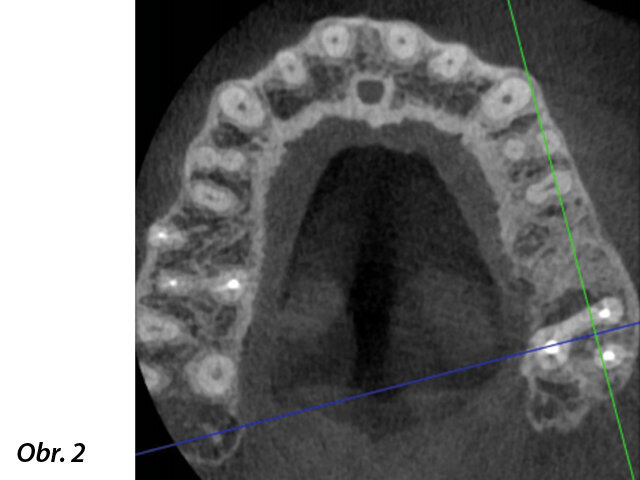

Klinický případ, kterým dále uvádím, je skvělým příkladem toho, jak obtížné je určit původ pacientových symptomů pouze na základě intraorálního snímku. Vizualizace 2D snímku selhává v jistotě určení přítomnosti léze, ještě důležitější však je, že je nemožné určit velikost, morfologii a typ léze, kterou se podaří nalézt. Analýza 3D snímku nám poskytne jasnou představu o klinické situaci: koronální a sagitální řezy odhalily přítomnost veliké léze sahající od apexu meziálního kořene tohoto moláru do furkace, zatímco axiální řezy nám umožňují provést přesnou analýzu endodontické anatomie a obzvláště pak tvaru meziálního kořene, který byl v tomto případě spojen s palatinálním kořenem. Celkový přehled o situaci ovlivňuje rozhodování o postupu a stanovení léčebného plánu zahrnujícího speciální úkony (obr. 1–4).